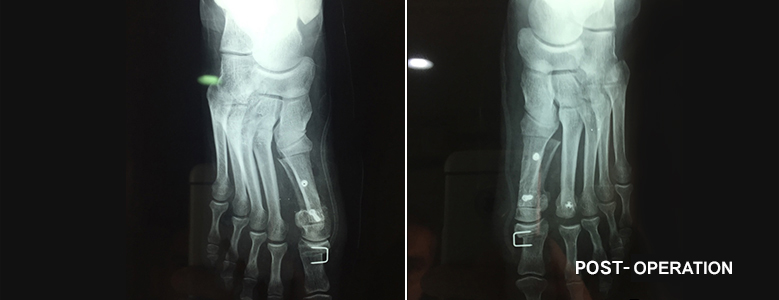

HALLUX VALGUS SURGERY

The surgery procedure is variable, adapted to the type of hallux valgus, to the first radius morphology ,metatarsal pallet and the existence of disorders of other toes.

Thus, new osteotomies (Scarf, Weil, Chevron ...) appeared giving the chance to make a three-dimensional correction of distortions by cutting and reorienting the bone with more reliable and longer lasting results. Meanwhile, the surgery aims to be less aggressive with the emergence of "minimally invasive" techniques and the advent of foot Percutaneous surgery mainly intended for small distortions or toe surgery.

A medical appointment for checking is usually scheduled one month after the intervention, with a radiograph, to allow you to walk without the special shoe and start physiotherapy.